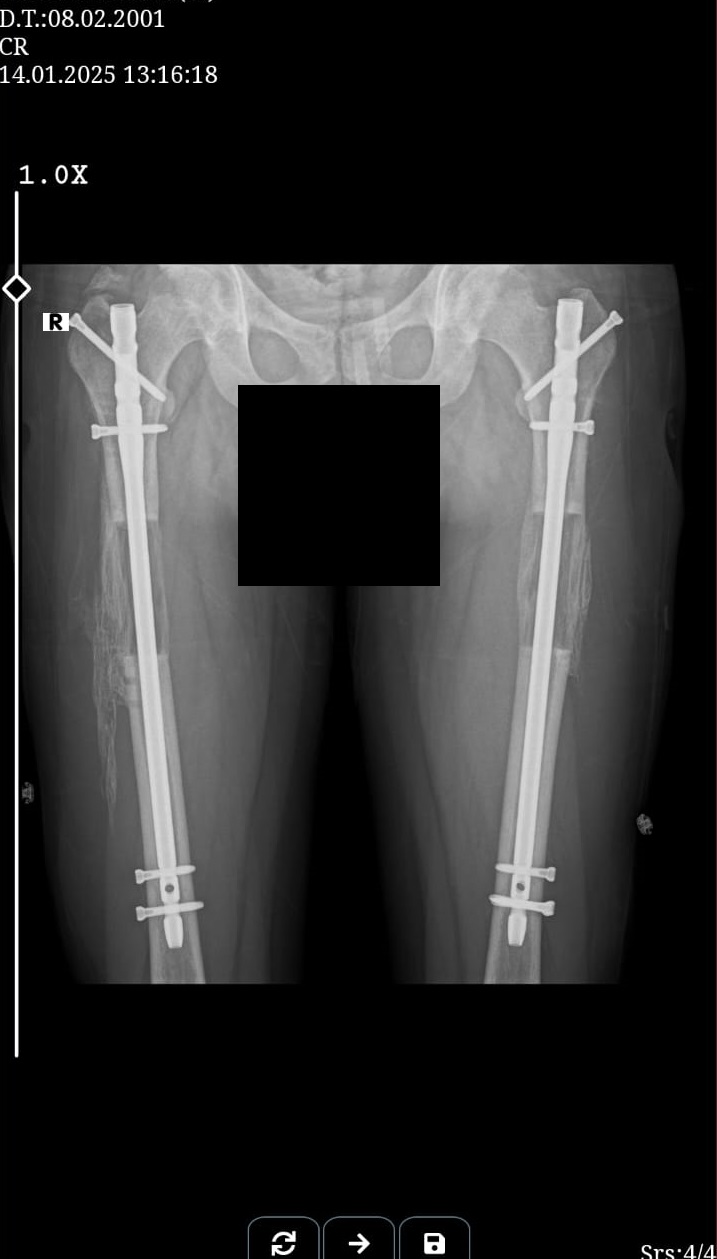

these are my xrays chronologically00 -

these are just before removing external fixatorAttachments: